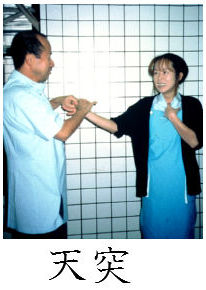

筋トーヌスを利用した生体センサーテスト。左手の人差し指で症状のある臓器代表点を刺激しておいて、右手の第一指(親指)と第二指(人差し指)で輪(Oーリング)を作り、持続的に力を入れさせて、検者がこの輪を開く力の強弱でその症状に対する噛み合わせの高さを決定。

のどに症状のある症例では臓器代表点として、天突を刺激します。